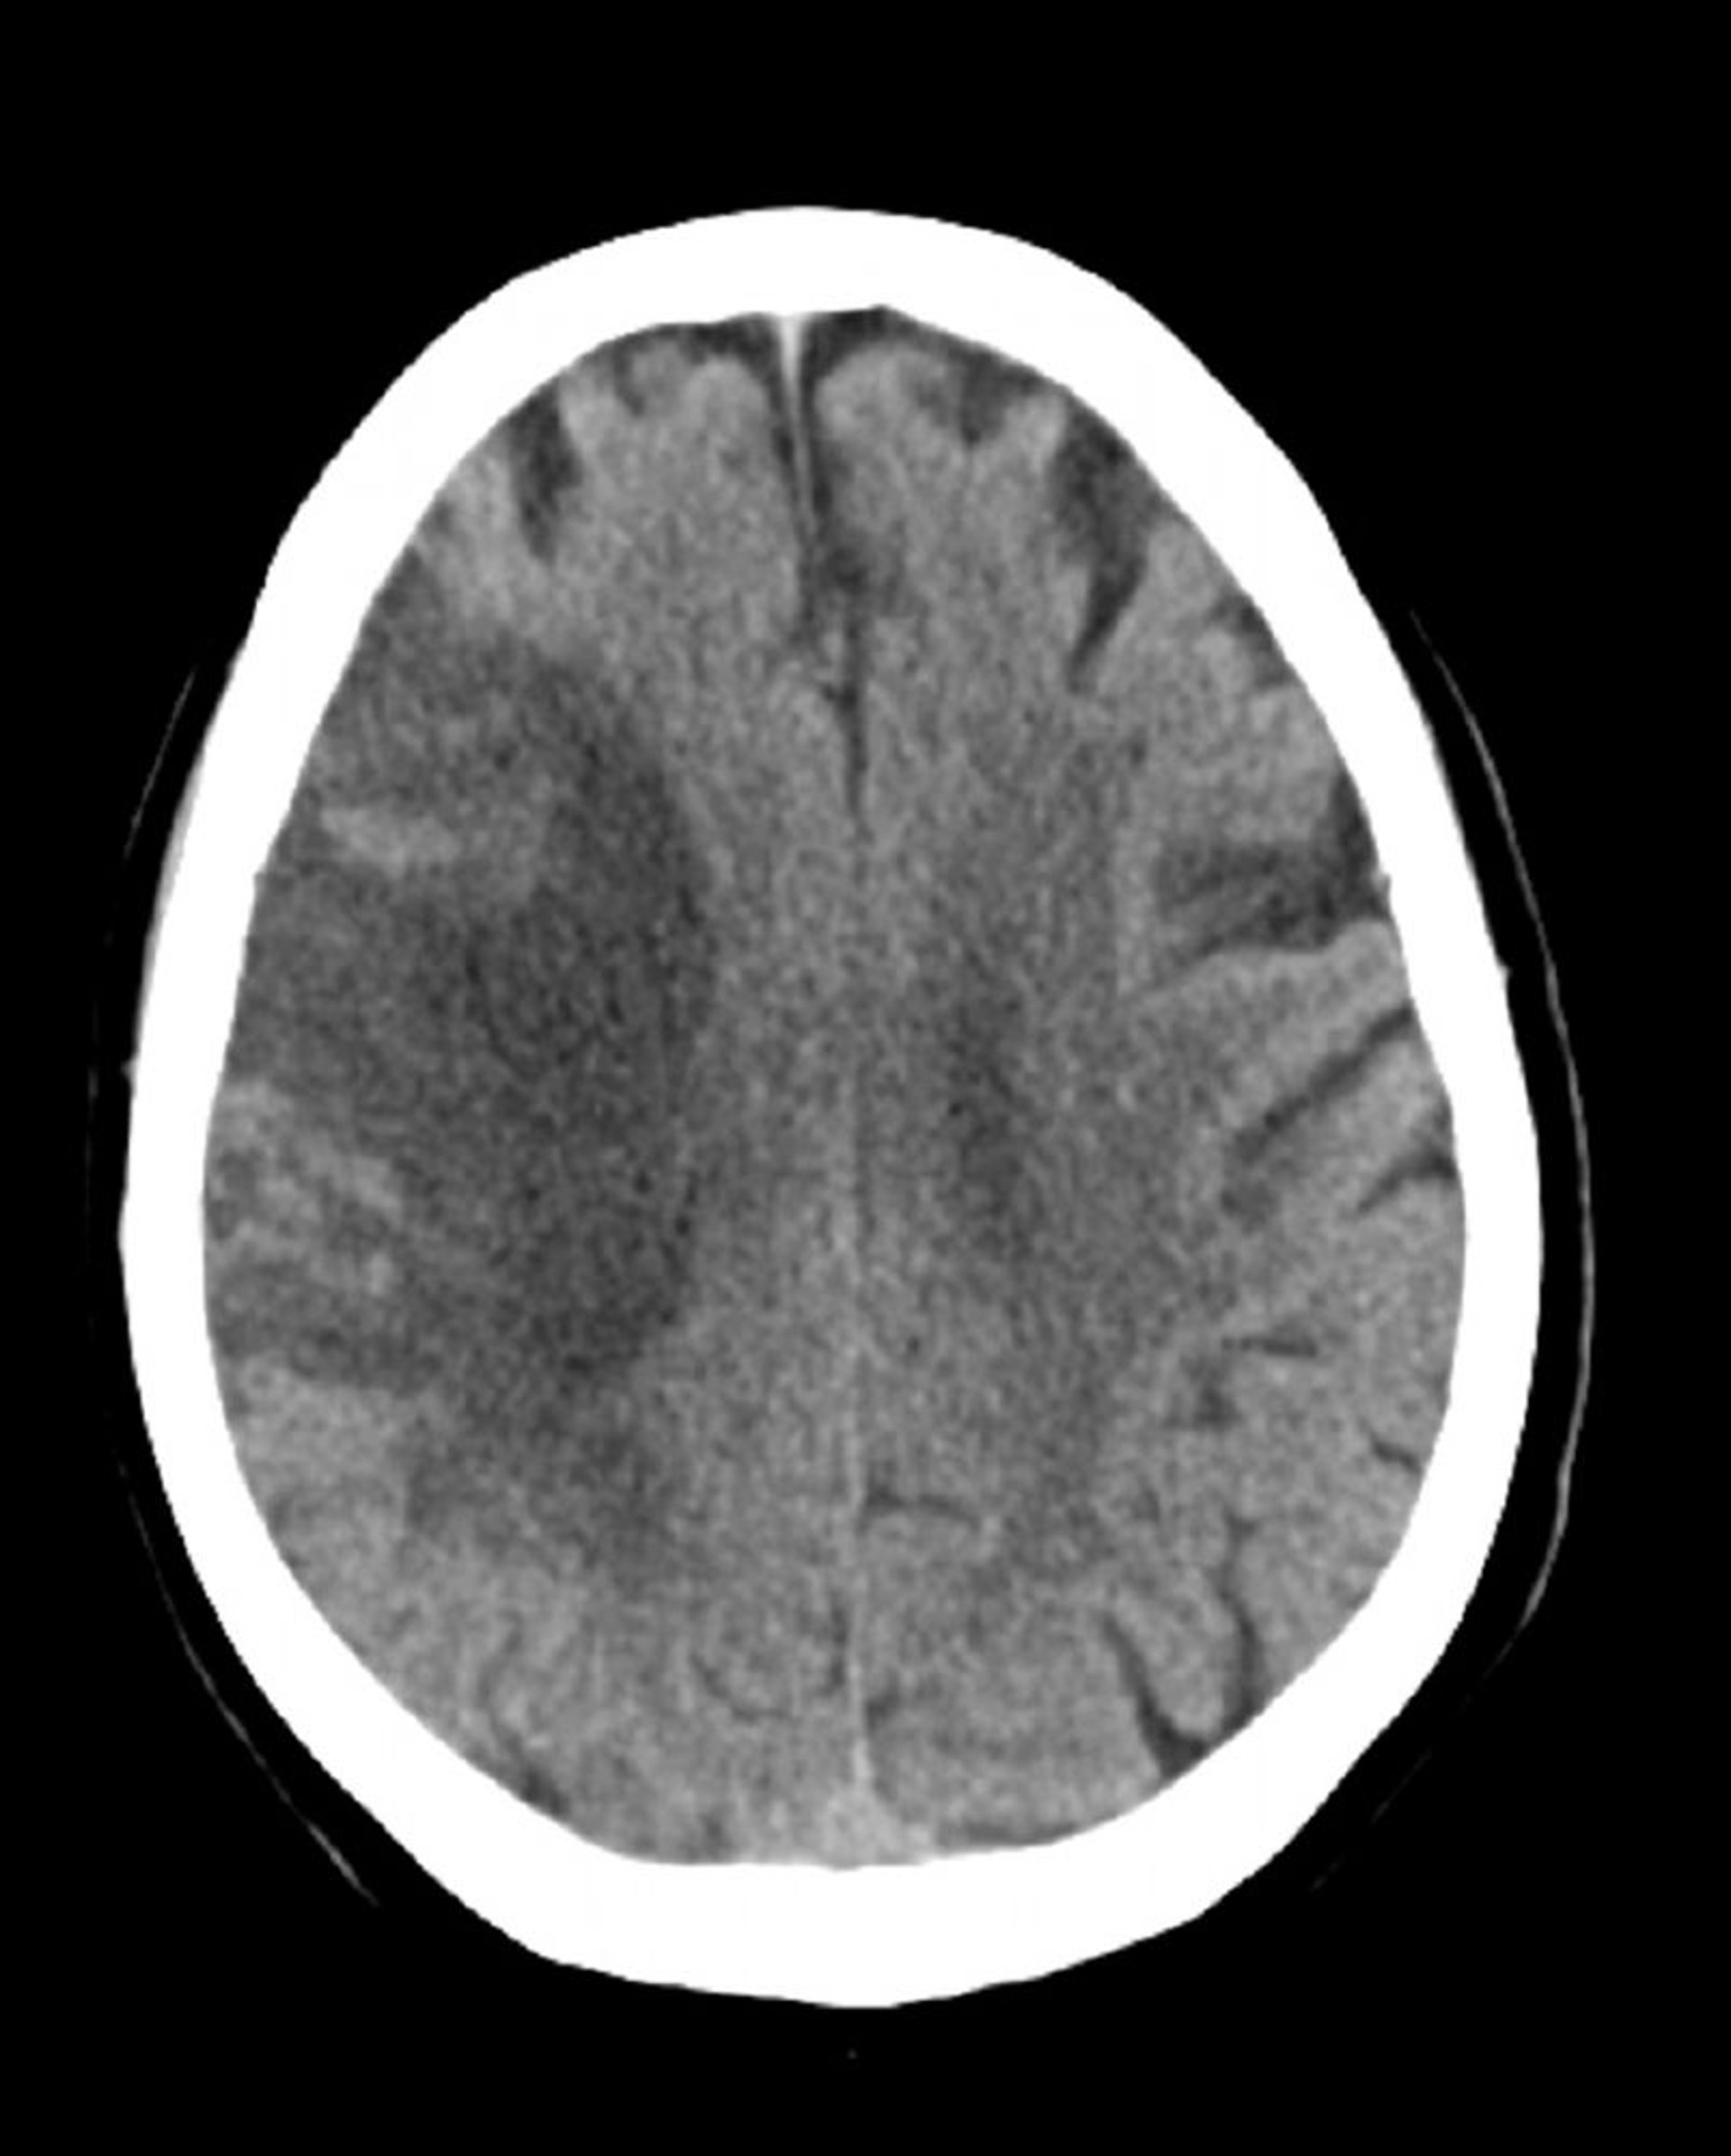

Infarto subacuto dell'arteria cerebrale media (TC)

Questa immagine mostra una bassa attenuazione nella distribuzione dell'arteria cerebrale media destra compatibile con un ictus ischemico subacuto con emorragia che si sviluppa in aree di ischemia.